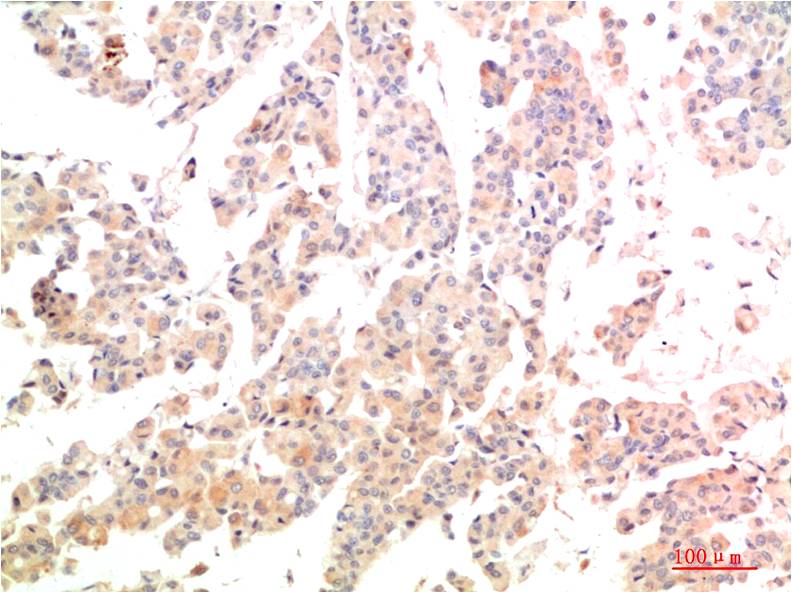

| Dilutions: | IHC 1:100-200 |